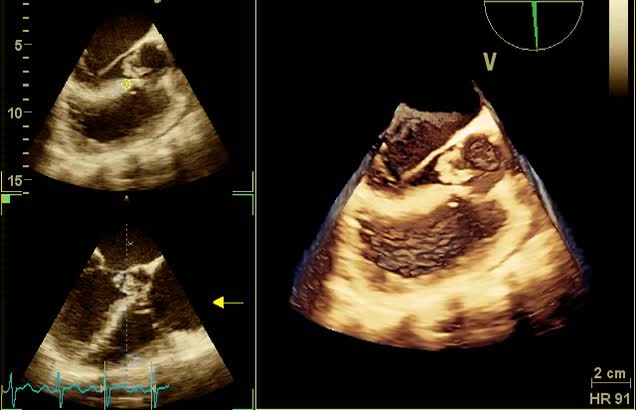

Distacco di protesi mitralica biologica

Manuela Muratori